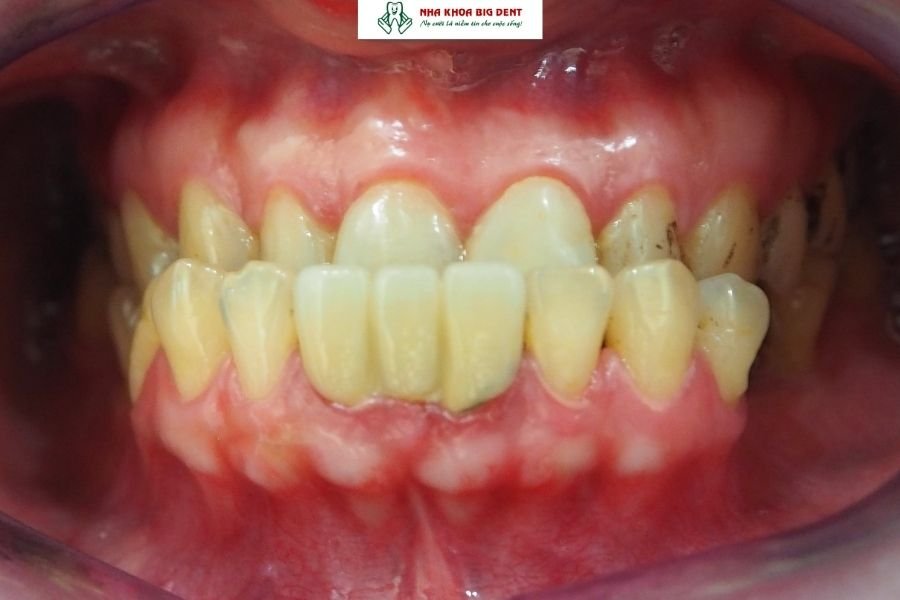

Răng móm (hay còn gọi là khớp cắn ngược hoặc sai khớp cắn hạng III) là tình trạng răng hàm dưới hoặc xương hàm dưới phát triển đưa ra trước quá mức so với hàm trên. Khi ngậm miệng, răng dưới phủ ra ngoài răng trên, khiến khuôn mặt mất cân đối, đặc biệt vùng cằm và môi dưới bị nhô ra.

- Khi khép miệng tự nhiên, răng dưới nằm phủ ra ngoài răng trên.